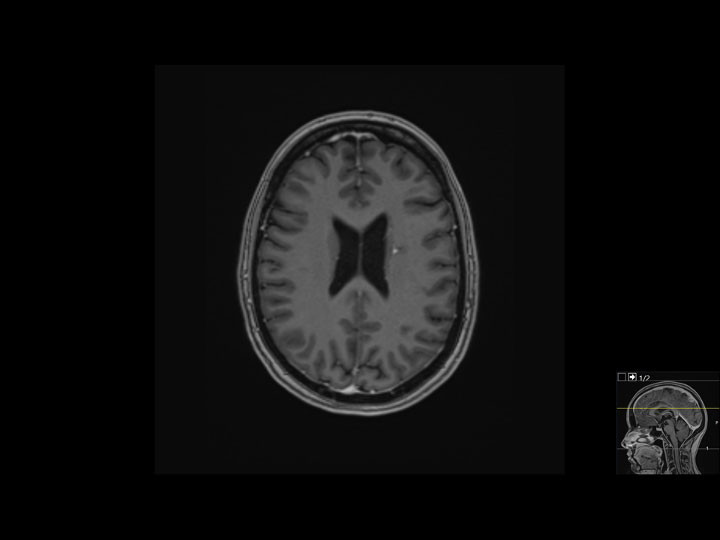

Pasienten var etter utskrivelse i psykisk bedring og gjenvant normalvekt. Etter initial systemisk behandling, som også inkluderte karboplatin og bevacizumab, mottok hun intravenøst pembrolizumab og pemetreksed hver tredje uke i totalt to år. Til å begynne med husket hun lite av det hun hadde gjennomgått. Hun har i ettertid uttrykt behov for å bearbeide og forstå det hun har vært gjennom, og minnene har gradvis dukket opp som «flashbacks». Prognose har vært et tema ved flere konsultasjoner, der pasienten spør om hun er frisk. Vi har svart henne at når hun fire år etter symptomdebut og to år etter behandlingspause ikke har tegn til residiv, gir det håp om langvarig effekt. Billedmessig har hun kun små restforandringer (figur 3). Pasienten bor nå i egen leilighet med barnet sitt, er arbeidssøkende og i funksjonsklasse 0 (ingen begrensninger i dagliglivet).